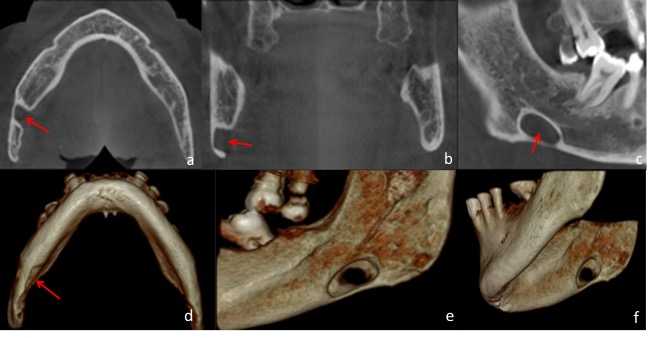

Paciente femenino de 51 años de edad, quien acudió a la consulta para evaluación del reborde alveolar previo a la colocación de implantes dentales. A la evaluación de la radiografía panorámica (Figura 3) se evidenció una imagen radiolúcida de límites definidos, bordes corticalizados, de forma ovoide, localizada en el cuerpo mandibular izquierdo, proxima a la basal mandibular, y proyectada sobre el canal mandibular. En el estudio por TCHC se observó en los cortes coronal y axial, una concavidad bien delimitada, formada a expensas de la tabla ósea lingual (Figura 4a-b). En el corte sagital (Figura 4c) y reconstrucciones 3D (Figura 4d-e) se evidenció la imagen hipodensa bien delimitada en la región antegonial, sin compromiso de la base de la mandíbula o el canal mandibular. La imagen muestró signos tomográficos compatibles con COS Tipo I.

Figura 4 FIGURA 4. Reconstrucciones multiplanares de Tomografía Computarizada de Haz cónico donde se observa en a, b y c, vistas coronal, axial y sagital respectivamente, en el lado izquierdo una imagen hipodensa, ovoide ubicada en proximidad al canal mandibular,cuya concavidad es dependiente de la tabla ósea lingual (Flechas rojas). En la reconstrucción volumétrica en vista lateral interna (d) e infero-superior (e), se observa la concavidad a expensas de la tabla lingual, la relación con el canal mandibular y el adelgazamiento de la base de la mandíbula.